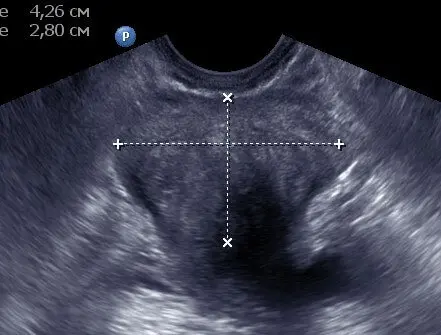

Рис.2. Доброякісна гіперплазія передміхурової залози (до лікування).

Мал. 3 Той же пацієнт через 14 днів від початку консервативної терапії.